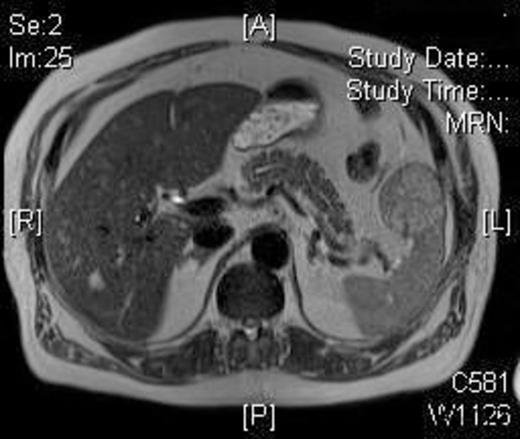

The operative time was 50 minutes and the blood loss was less than 20 ml. The patient made an uneventful recovery and was discharged on the second postoperative day. Histology demonstrated complete excision of a LCA with no cell atypia. A 3-month postoperative MRI showed no disease recurrence and normal appearance of the splenic remnant [Figure 3].